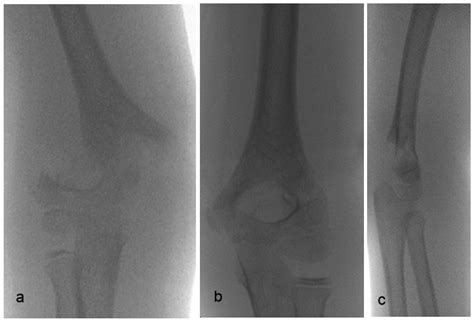

Diagnosing Supracondylar Humerus Fractures

Diagnosing a supracondylar humerus fracture involves a thorough physical examination and imaging studies. The healthcare provider will assess the elbow for signs of injury, such as swelling, deformity, and tenderness. Imaging studies, such as X-rays, are crucial for confirming the diagnosis and determining the type and severity of the fracture.

X-rays are typically taken from multiple angles to provide a comprehensive view of the fracture. In some cases, additional imaging studies, such as a CT scan or MRI, may be necessary to assess the extent of the injury and plan the appropriate treatment.

Supracondylar humerus fractures are classified based on the direction of the fracture line and the displacement of the bone fragments. The most commonly used classification system is the Gartland classification, which includes three types:

Type Description

Type I Non-displaced fracture with minimal angulation

Type II Displaced fracture with posterior angulation of the distal fragment

Type III Completely displaced fracture with no cortical contact between the fragments